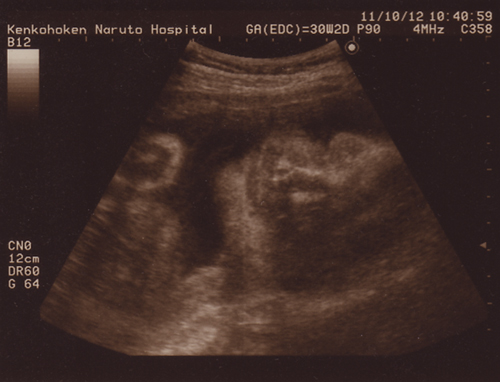

なんだかむふふ顔ーーー(´▽`)

わかります?

右側が頭の上ね。寝転んでむふ♪って笑ってるみたい。

左の丸いのは手です。

顔の前でうにゃうにゃ動かしてました。

ちゃんと指も閉じたり開いたり見えるんだよ。

なんだか、またおとうぱんに似ている気がする。。。